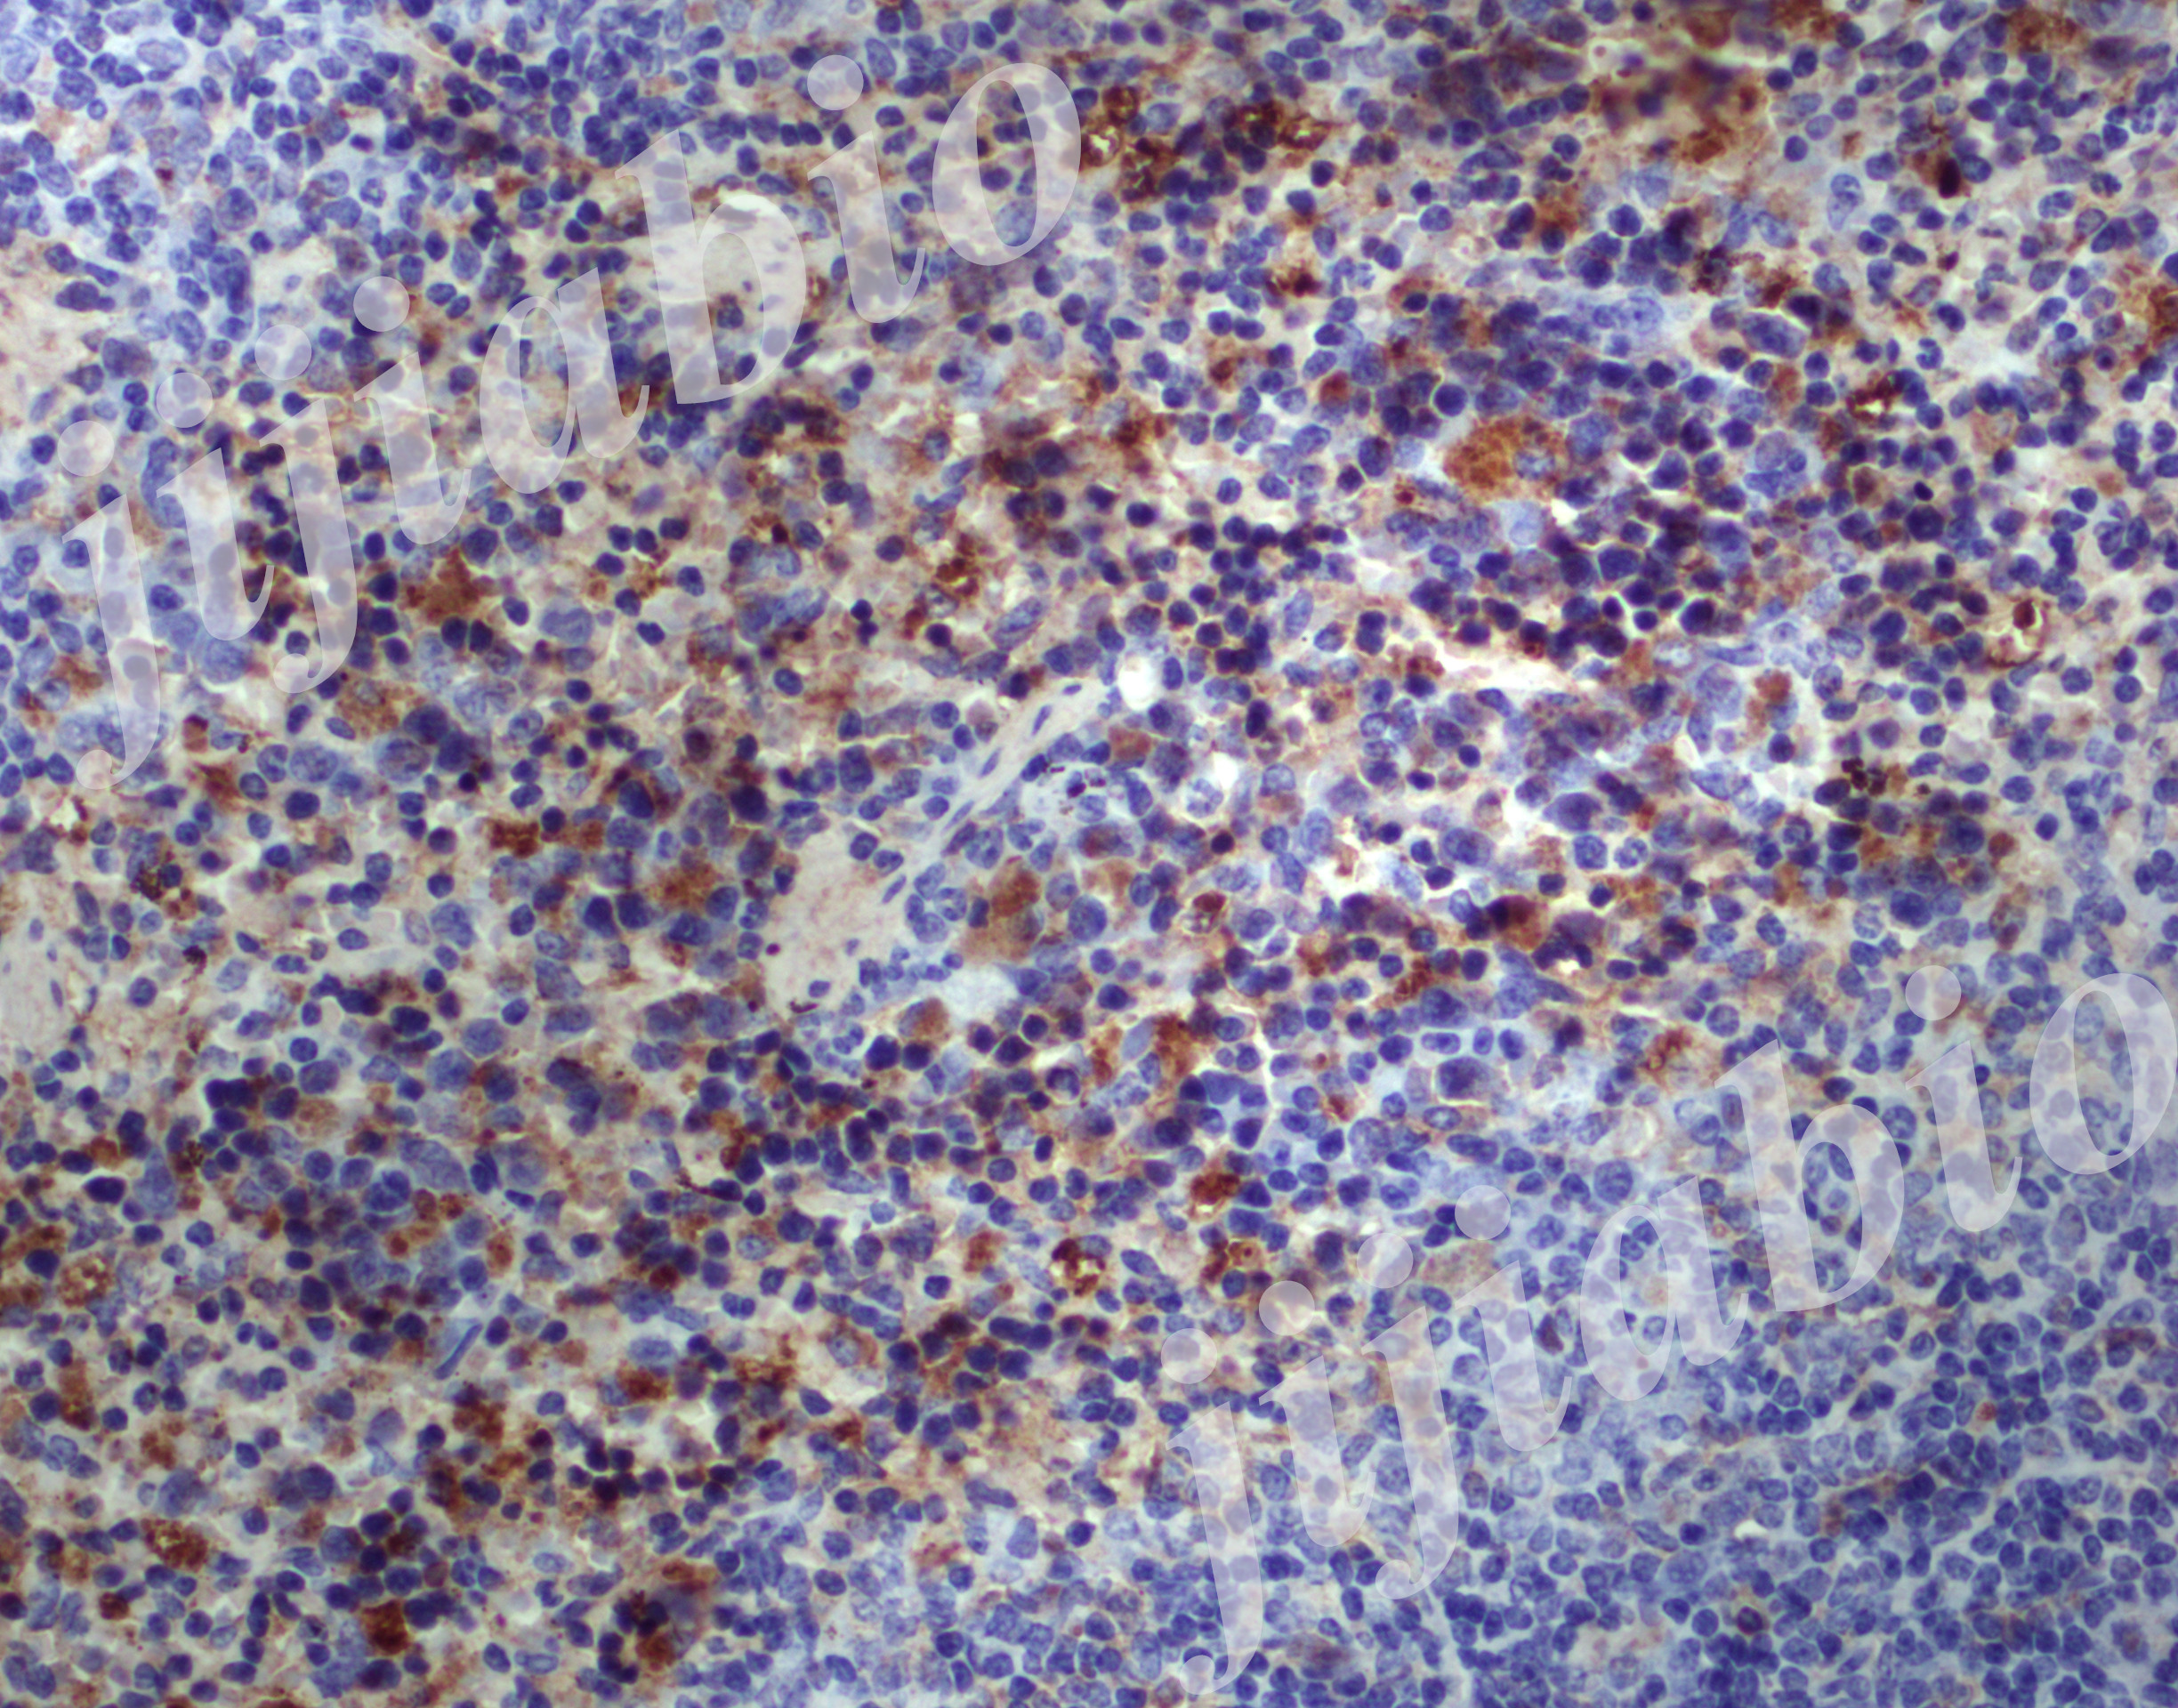

8周 脾 icos 40-001.jpg

免疫组化,是应用免疫学基本原理——抗原抗体反应,即抗原与抗体特异性结合的原理,通过化学反应使标记抗体的显色剂(荧光素、酶、金属离子、同位素)显色来确定组织细胞内抗原(多肽和蛋白质),对其进行定位、定性及定量的研究,称为免疫组织化学技术(immunohistochemistry)或免疫细胞化学技术(immunocytochemistry)。